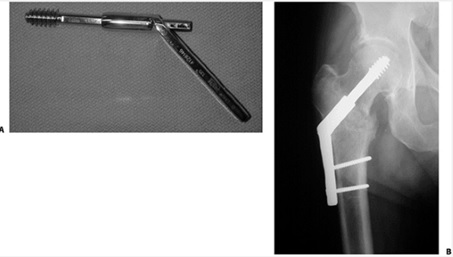

* درمان تيپ III : اين سناريويي نادر است. بيمار بيشتر با علايم درد و آزردگي خفيف و خستگيپذيري زودرس هيپ مبتلا در پيادهروي مراجعه مينمايد. درمان اين تيپ انجام سوراخهاي متعدد در گردن فمور تا سر فمور با عبور از محل نانيونيون براي باز كردن كانال مدولر در محل نانيونيون فيبرو و ايجاد كالآندوستال است كه يا با پيچهاي كانوليتد (Canulated Screw) يا با DHS انجام خواهد شد.

نانيونيون فيبرو بدون از دست رفتن فيكساسيون يا دفورميتي مشخص